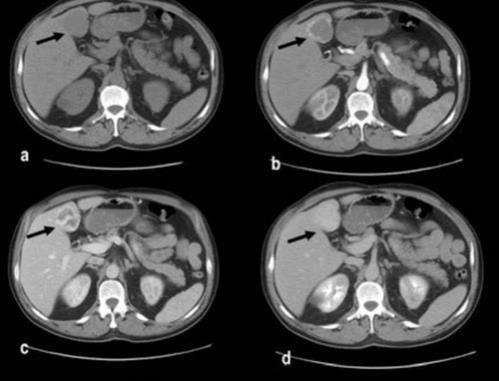

El principal factor de riesgo para su desarrollo es la cirrosis, principalmente la relacionada con la hepatitis viral crónica. Es este caso la hepatitis C, cirrosis alcohólica, cirrosis causada por hemocromatosis y cirrosis biliar primaria. La mayor parte de los casos en esta zona están relacionados con el virus de la hepatitis B, asociado o no con aflatoxina (micotoxinas producidas por dos especies de Aspergillus, un hongo localizado en especial en zonas con climas cálidos y húmedos). En el estudio de tomografía multicorte con técnica multifase el carcinoma hepatocelular (CHC) tiene vascularización predominantemente arterial, lo que determina un patrón de comportamiento específico caracterizado por un intenso reforzamiento en fase arterial, seguida de un lavado (washout) rápido en fase venosa portal, y en muchos casos la presencia de una seudocápsula en fases tardías. Este patrón ha resultado ser específico para el diagnóstico de carcinoma hepatocelular.(17-18)

El CHC presenta una vascularización predominantemente arterial (por neovascularización) a medida que avanza el proceso de hepatocarcinogénesis, a diferencia del parénquima hepático, en donde la vascularización es mixta: arterial y portal. Este patrón característico, favorecido por la alta probabilidad del CHC en pacientes con hepatopatía crónica, ha mostrado una especificidad próxima al 100% para el diagnóstico de CHC. No obstante, este patrón vascular está penalizado por una sensibilidad del 60%-70% en lesiones de pequeño tamaño, y se ha descrito que alrededor de un 15% delos CHC de pequeño tamaño son hipovasculares al no haber desarrollado aún su neovascularización, sin que ello indique que estas lesiones tengan un comportamiento menos agresivo.(18-21) No obstante, en ocasiones el carcinoma hepatocelular puede ser hipovascular y no mostrar reforzamiento intenso en la fase arterial, siendo en estos casos muy importantes las fases venosas portal y venosa tardía, en donde la lesión permanece hipodensa o incluso puede presentar un comportamiento atípico con importante reforzamiento en la fase arterial y ausencia de lavado tardío (Anexos 10 y 11).